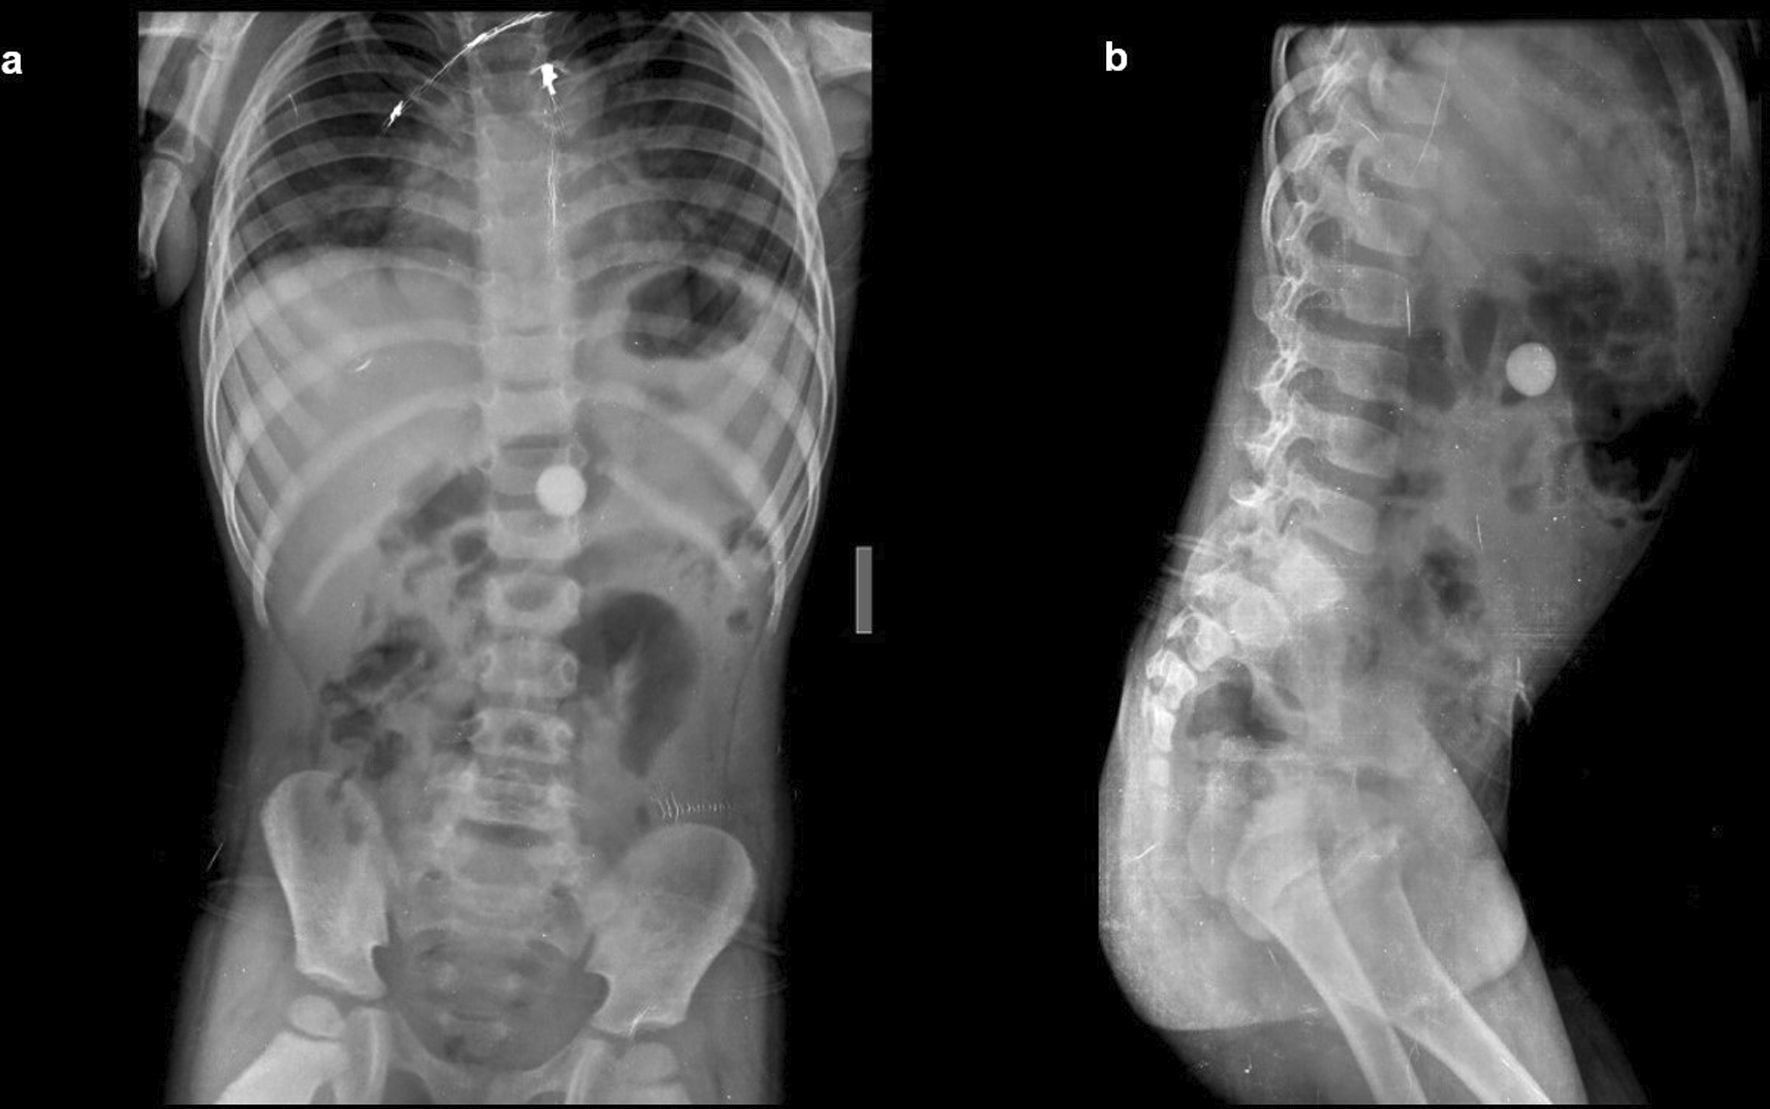

Case 1: A four-year-old child came with a history of abdominal pain for 5–6 hours. A clinical examination revealed soft to touch abdomen that was unremarkable. On a radiograph of the abdomen, frontal and lateral projections reveal circular radio opacity on the left side at the level of the L2-L3 disc suggestive of coin, which the patient had accidentally ingested. It passed through the gastro-intestinal tract without a problem.

Case 2: A 34-year-old male carpenter by profession accidentally ingested a screw before 3 days. He had mild, intermittent pain in the right iliac fossa. The clinical examination revealed no significant findings. A radiograph of the abdomen in frontal and lateral views reveals a nail at the level of the L4 and L5 vertebrae in the gastrointestinal tract, which passed without any problems.

The swallowing of foreign bodies is a common condition in children and mentally challenged individuals.3–5 Fortunately, most ingested objects move through the digestive system without causing any problems (Figure 1a,b). Sharp and elongated objects can pass uneventfully (Figure 2a,b); however, they can pierce the mucosal lining and seriously damage or completely perforate the intestinal wall (Figure 3a-e). The object may just partially puncture the gut wall, resulting in a chronic inflammatory condition with few symptoms that is diagnosed months or years later.5–7